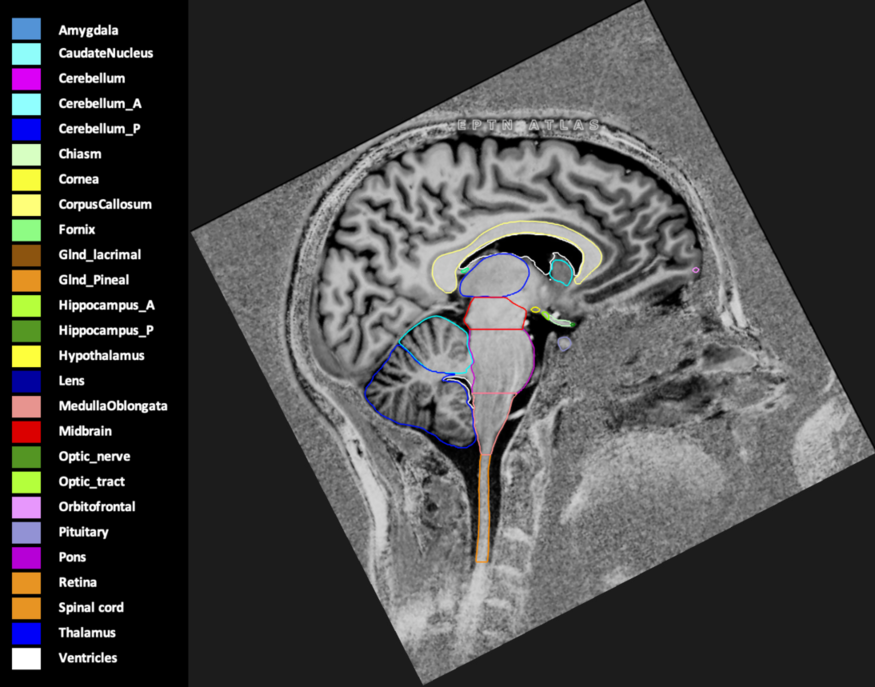

Eekers et al. have published an international neurological atlas for contouring of organs at risk in consensus with the European Particle Therapy Network (EPTN) in 2018 and an update in 2021. The purpose of this consensus atlas is to decrease inter- and intra-observer variability in delineating OARs relevant for neuro-oncology.

Included are all OARs known to be relevant for radiation-induced toxicity in neuro-oncology: brain, brainstem (midbrain, pons, medulla oblongata), chiasm, cerebellum (anterior & posterior), cochlea, cornea, hippocampus (anterior & posterior), hypothalamus, lens, lacrimal gland, optic nerve, pituitary, skin, and vestibular & semicircular canals. To further facilitate research on cognition, vision and radiological changes after irradiation of the brain, potential clinically-relevant OARs are included: amygdala, caudate nucleus, cerebellum (anterior & posterior), corpus callosum, fornix, macula, optic tract, orbitofrontal cortex, periventricular space (PVS), pineal gland, and thalamus.

Three-dimensional delineation of the 25 consensus OARs for neuro-oncology are shown on CT (WW/WL 120/40, 3000/600), 3T MR images, (T1Gd, T2FLAIR 1mm) and 7T MR (MP2RAGE 0.7 mm). All are presented in transversal, sagittal and coronal view.